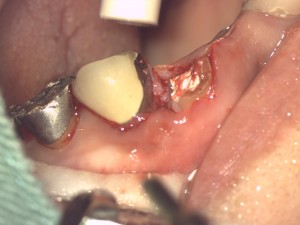

こちらの患者さんはブリッジが不適合のため虫歯が広がり切り株のような状態になりました。

このままでは抜歯ですが根を外の世界に引き出してくる方法があります。

切り株のようになった根にただ差し歯にしても脱落、歯根破折という結果を招きますのでこのような外科処置が必要になります。

この処置を歯冠延長法(Crown Length Procedure)と言います。